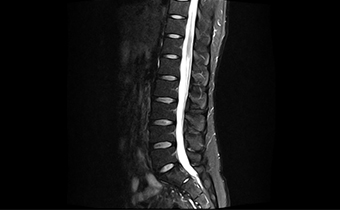

能在1秒内完成对任意部位,任意区域的快速精准匀场。磁场均匀度可达0.002ppm。在极速匀场过程中,几乎不受运动伪影的影响。

呈现大FOV、偏中心优质图像;实现大范围压脂成像,缩短压脂序列时间

改善脂肪抑制效果,减小DWI图像伪影。改善SWI等对B0涡流敏感序列的图像质量